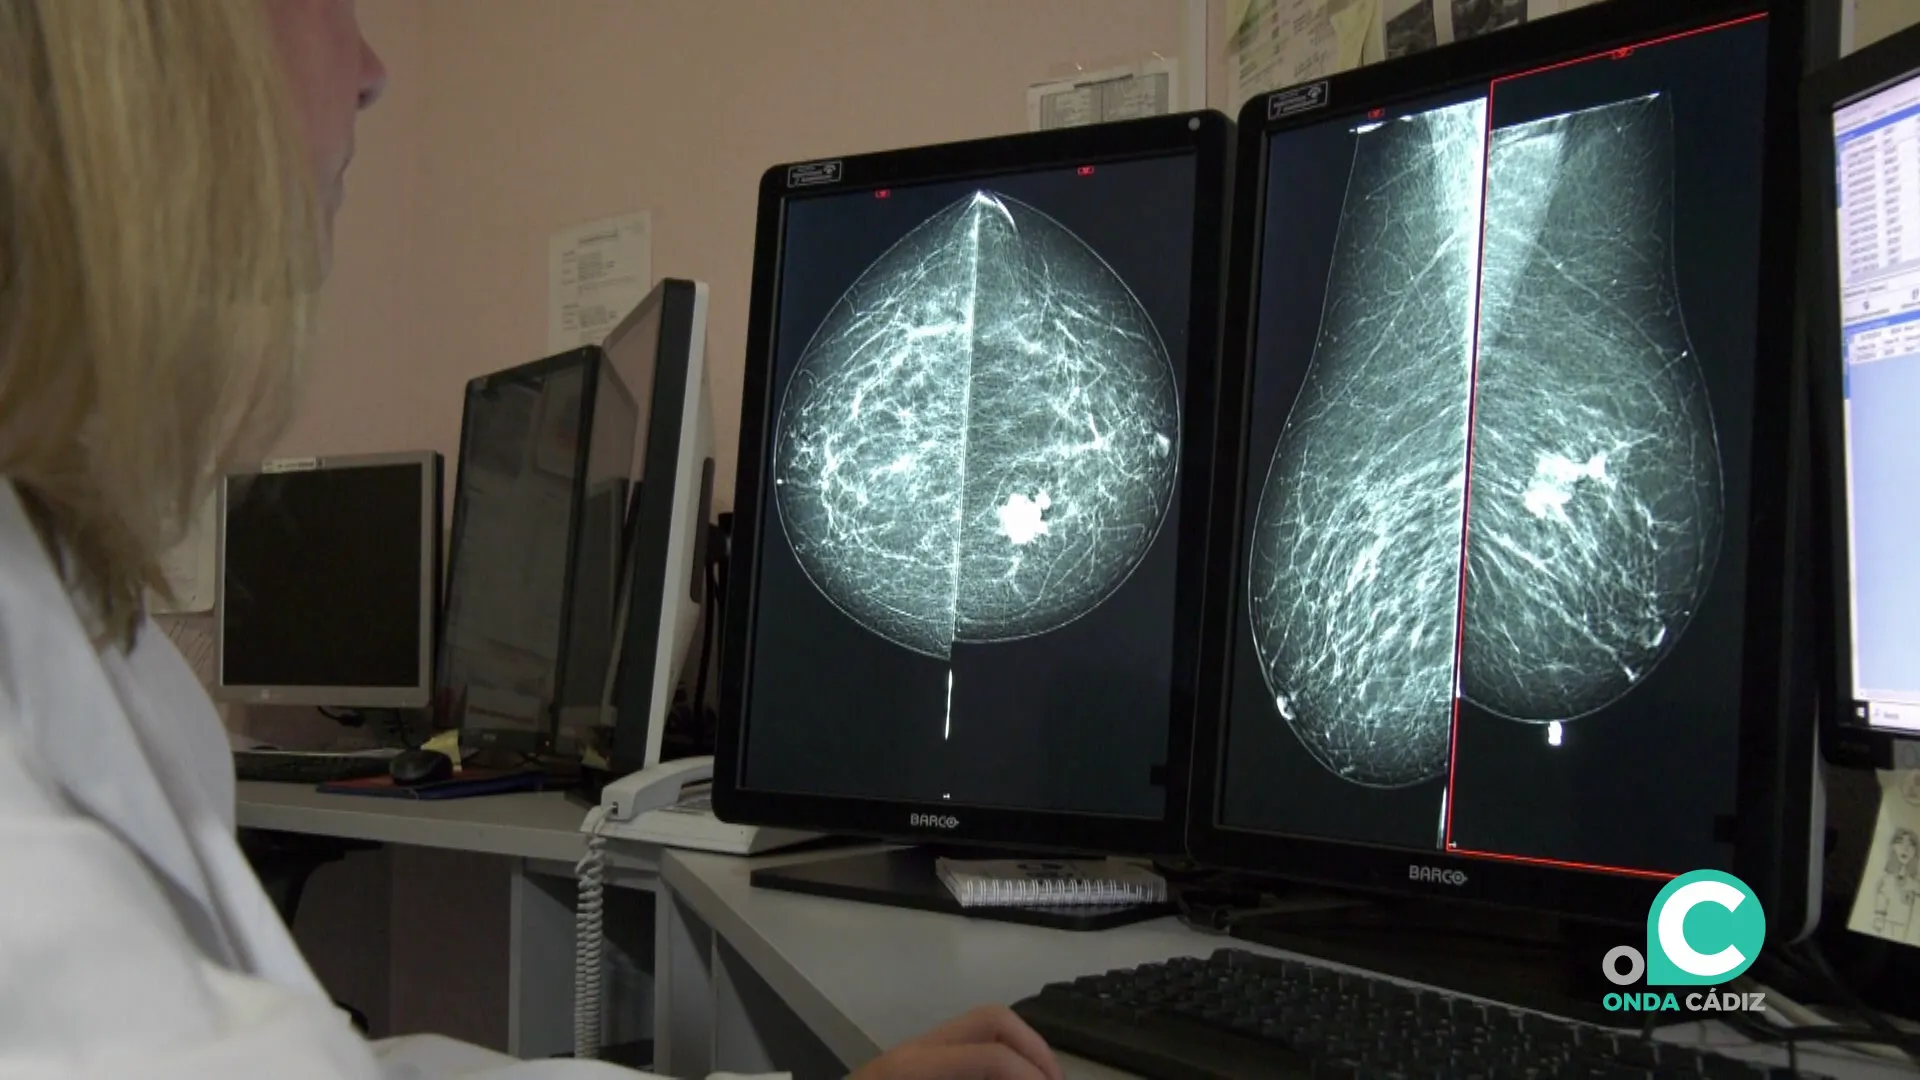

Estudio de una mamografía